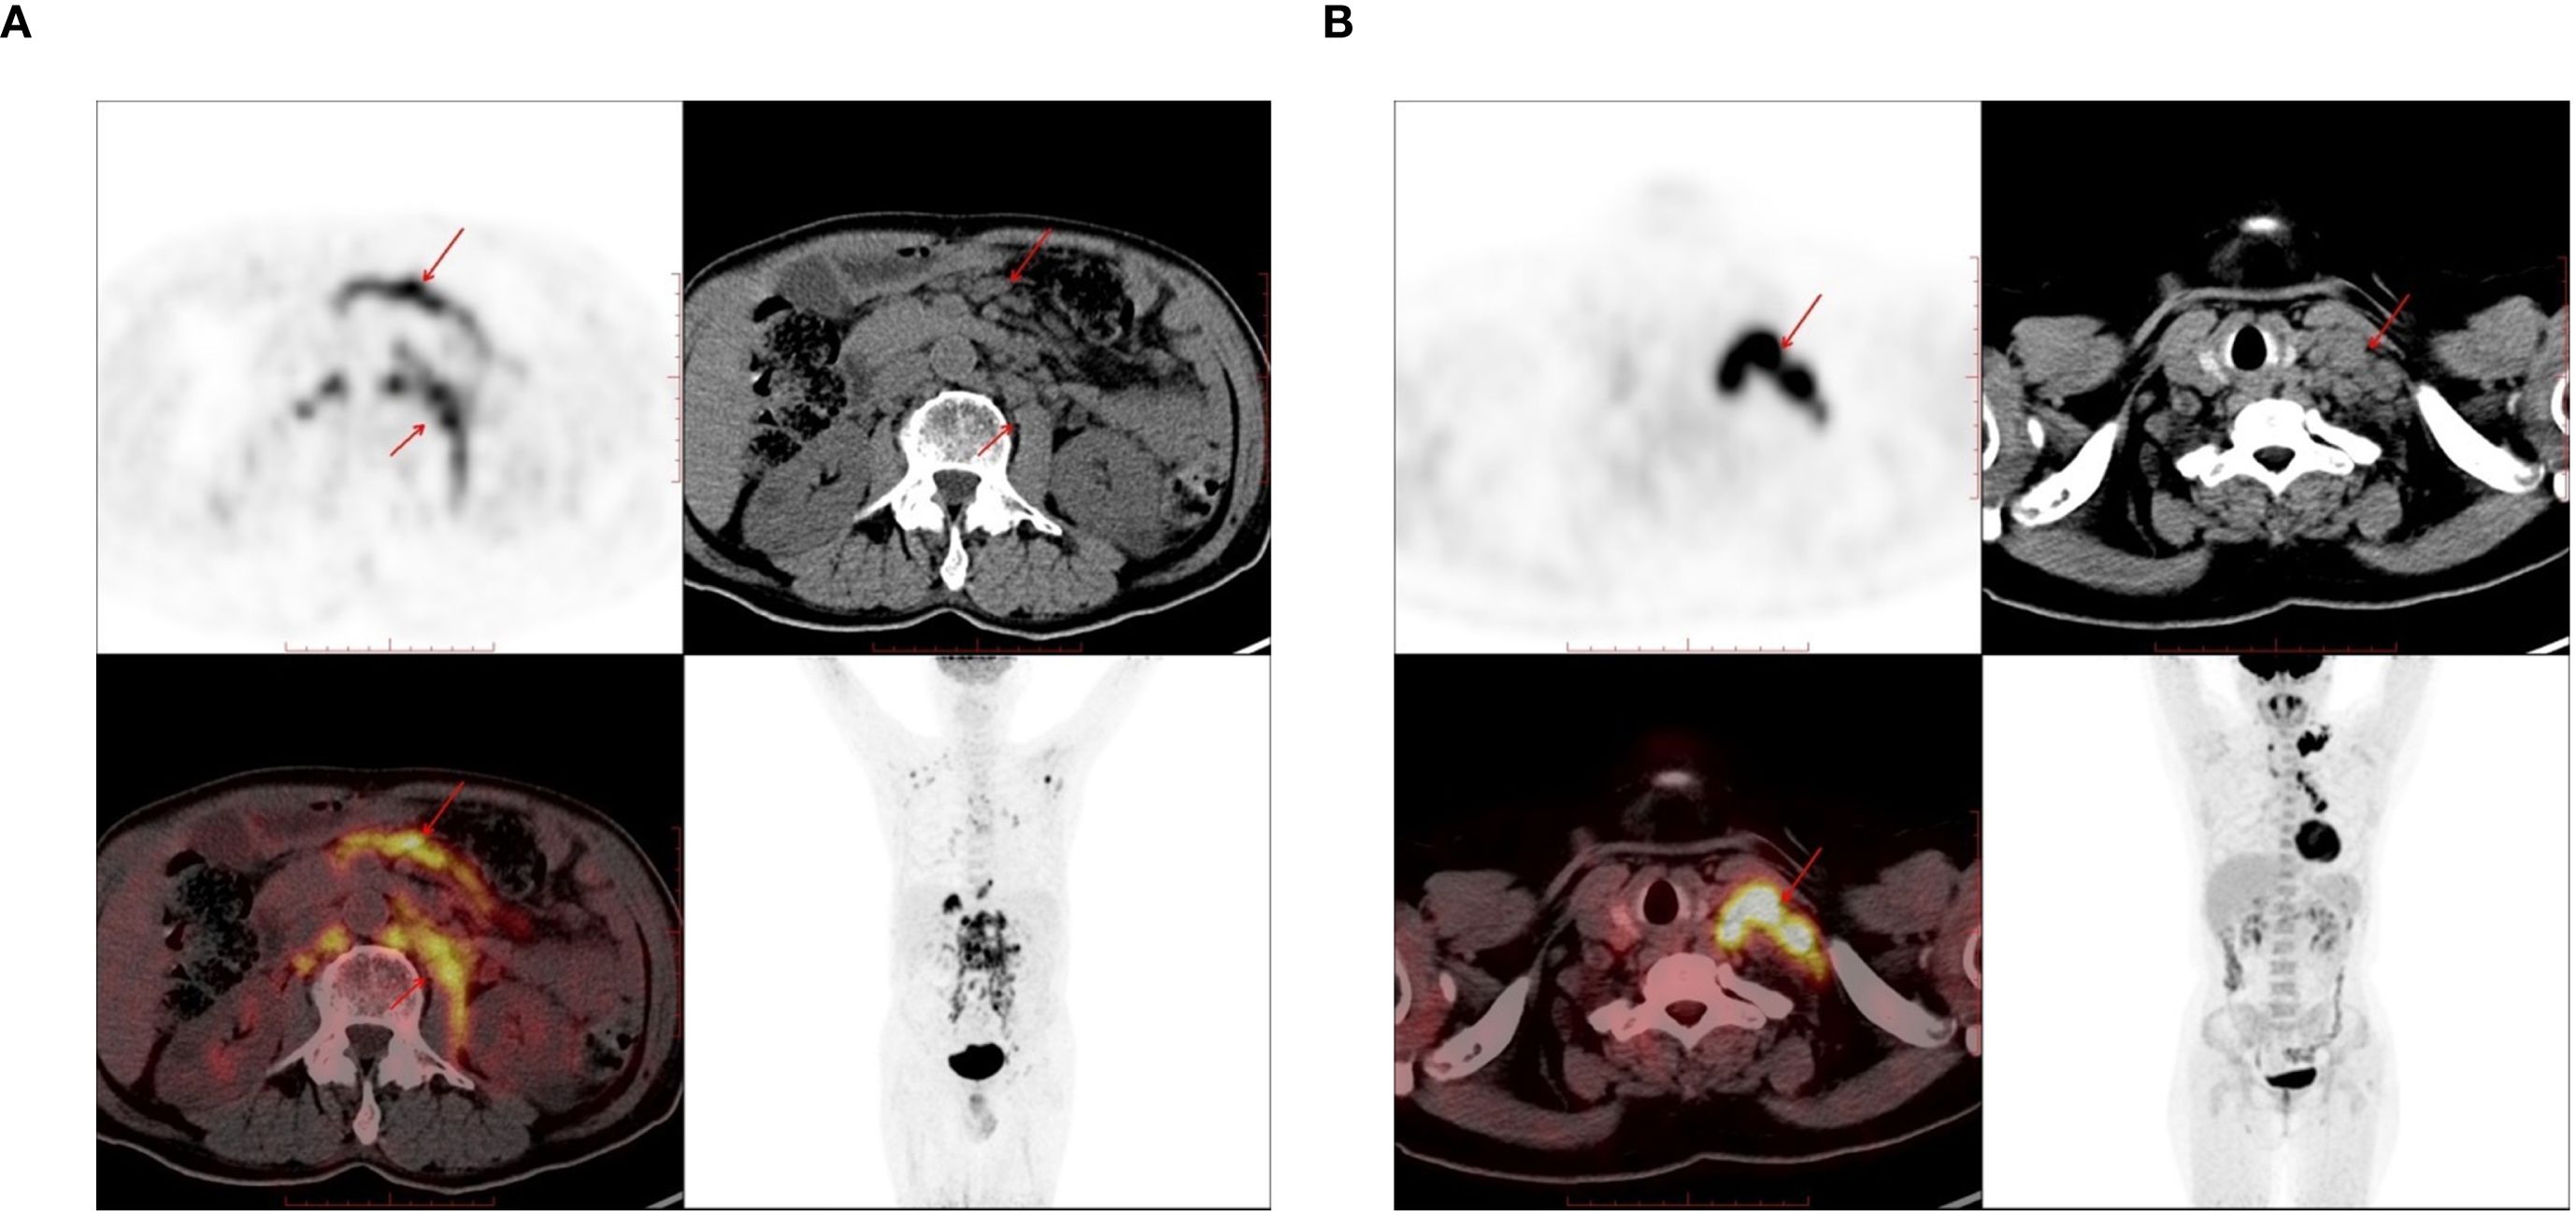

A total of 116 lymphoma-involved nodes and 131 metastatic nodes were analyzed. Significant disparities in PET/CT biomarkers were observed between the two groups. Specifically, lymphoma-involved nodes demonstrated markedly higher metabolic activity, with a significantly elevated median SUVmax (21.4 vs. 8.9; p < 0.001) and larger short-axis diameter (3.2 cm vs. 1.8 cm; p < 0.001). Systemic involvement in the DLBCL group was further evidenced by a higher rate of splenomegaly (43.6% vs. 8.7%; p < 0.001) and significantly increased splenic SUVmax (4.1 vs. 2.3; p = 0.002). In contrast, conventional CT morphological features such as the presence of necrosis or calcification did not differ significantly between groups. Bone destruction was rare in both cohorts and not statistically different. Representative PET/CT manifestations of lymphomatous and metastatic nodal involvement are illustrated in Figure 1. These findings underscore the value of PET-derived metabolic parameters, particularly nodal SUVmax and splenic metrics, as robust discriminators between DLBCL and metastatic nodal disease, supporting their inclusion as key features in subsequent predictive modeling.

Figure 1. The PET-CT images used in the study. (A) 72-year-old male, there are enlarged lymph nodes in the abdominal cavity and retroperitoneum, which were pathologically diagnosed as diffuse large B-cell lymphoma (DLBCL). (B) A 61-year-old female, there are enlarged lymph nodes in the left supraclavicular region, which was pathologically diagnosed as lung adenocarcinoma.